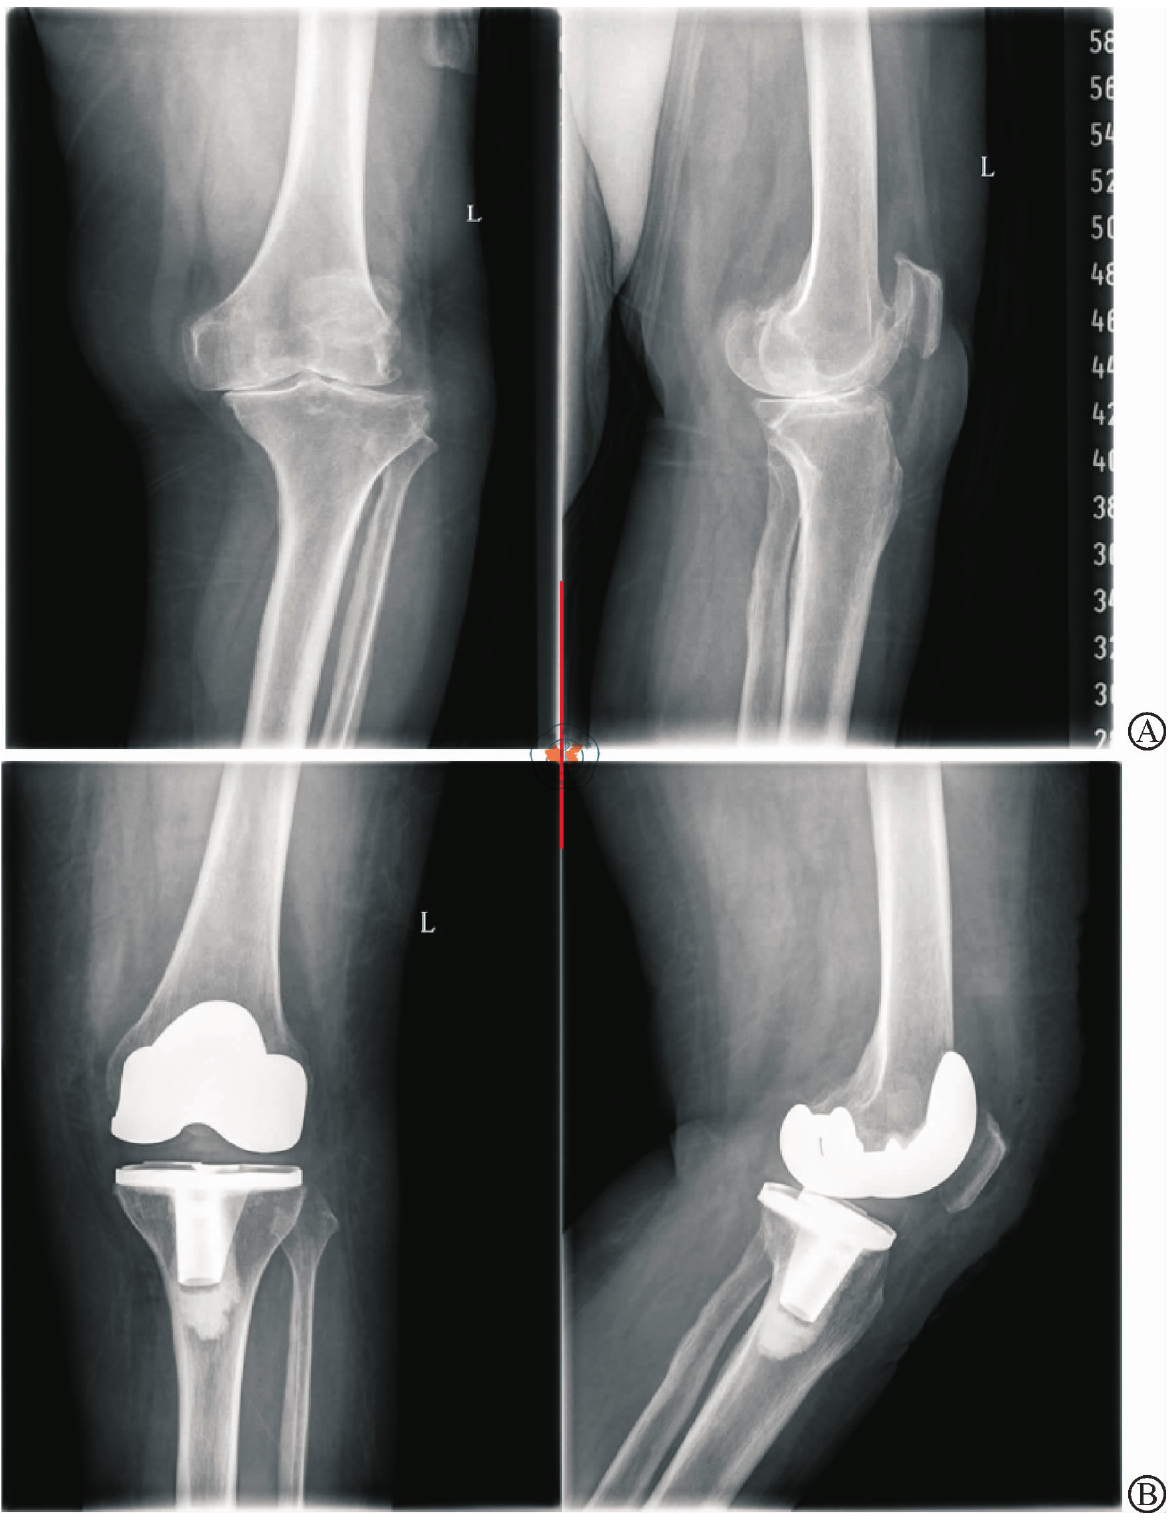

Application value of fixed and mobile platform prostheses in total knee arthroplasty

To compare the early effects of fixed platform prosthesis and mobile platform prosthesis in total knee Joint replacement (TKA).

Eighty five patients who had been treated with TKA in the Department of Orthopaedics and Traumatology of Fangshan District Hospital of Traditional Chinese Medicine from June 2019 to June 2021 were retrospectively selected. They were divided into fixed platform prosthesis group (n=40) and mobile platform prosthesis group (n=45) according to the different applications of platform prosthesis during surgery. Perioperative indicators and the incidence of complications within six months after surgery were collected. the knee joint score (HSS), visual analogue score (VAS), and gait spatiotemporal parameters of the New York Special Surgery Hospital before surgery and three and six months after surgery were comparee between the two groups.

There was no statistically significant difference in intraoperative bleeding volume, surgical time, hospital stay, pad dislocation rate, and complication incidence between the two groups (P>0.05). At different time points, the stride length, stride speed, and single support phase of the affected side in the fixed group were higher than those in the active group, with statistically significant differences (F=21.203, 9.282, 20.388, all P<0.05). After three months of surgery, the stride length, stride speed, and single support phase of the affected side in the active group were higher than those in the fixed group (t=3.904, 14.725, 7.756, all P<0.05).

Both mobile and fixed platform prostheses can achieve gait improvement and satisfactory surgical results. Mobile platform prostheses in TKA may provide faster postoperative gait improvement, which can better promote early exercise and knee joint function recovery.